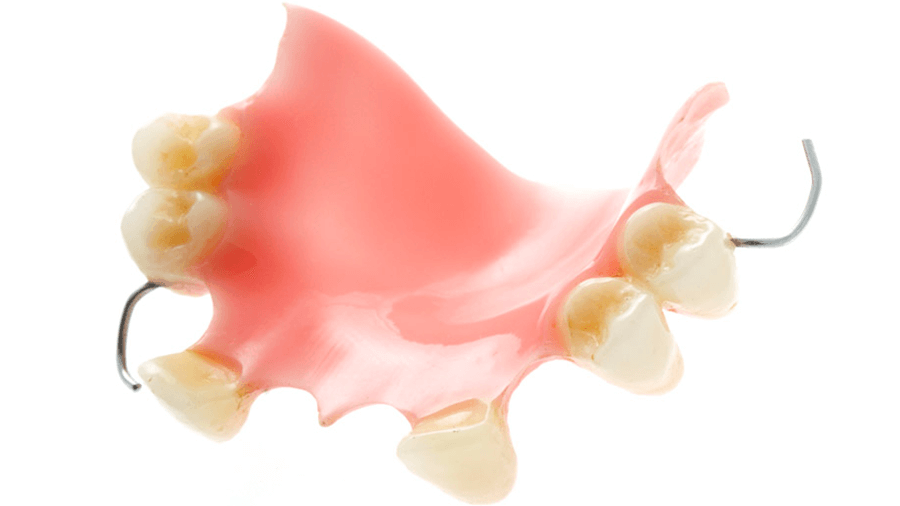

Съемные профилактические протезы: примеры и фотографии